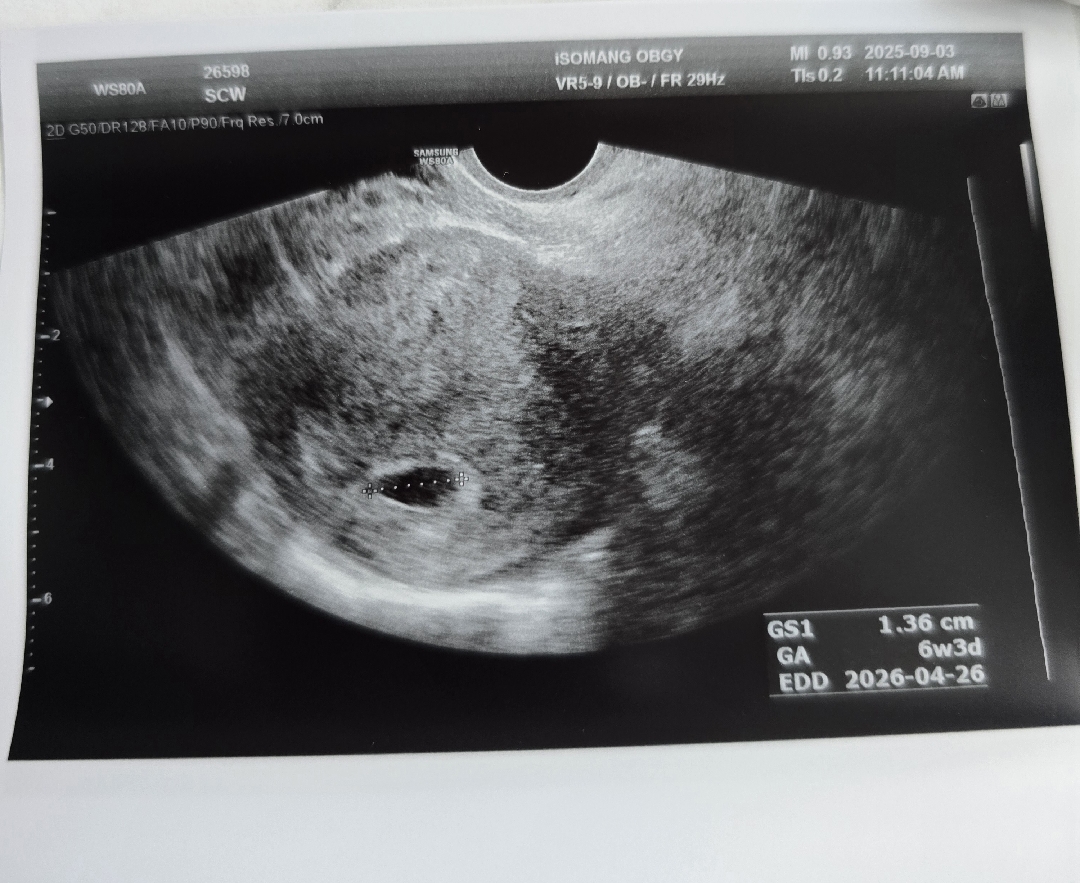

2번에 화유끝에 소중한아이가 찾아왔는데요 피검수치는 755,5주5일차에 아기집도 0.38>1.36cm 커졌어요!! 하루빨리 아기심장 소리 듣고싶은데 잘크고있겠죠!?